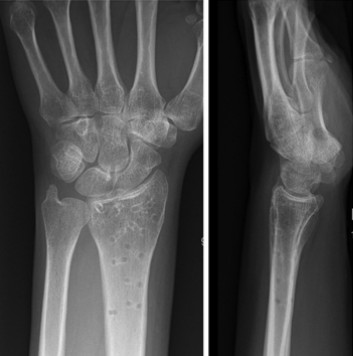

Primer ③